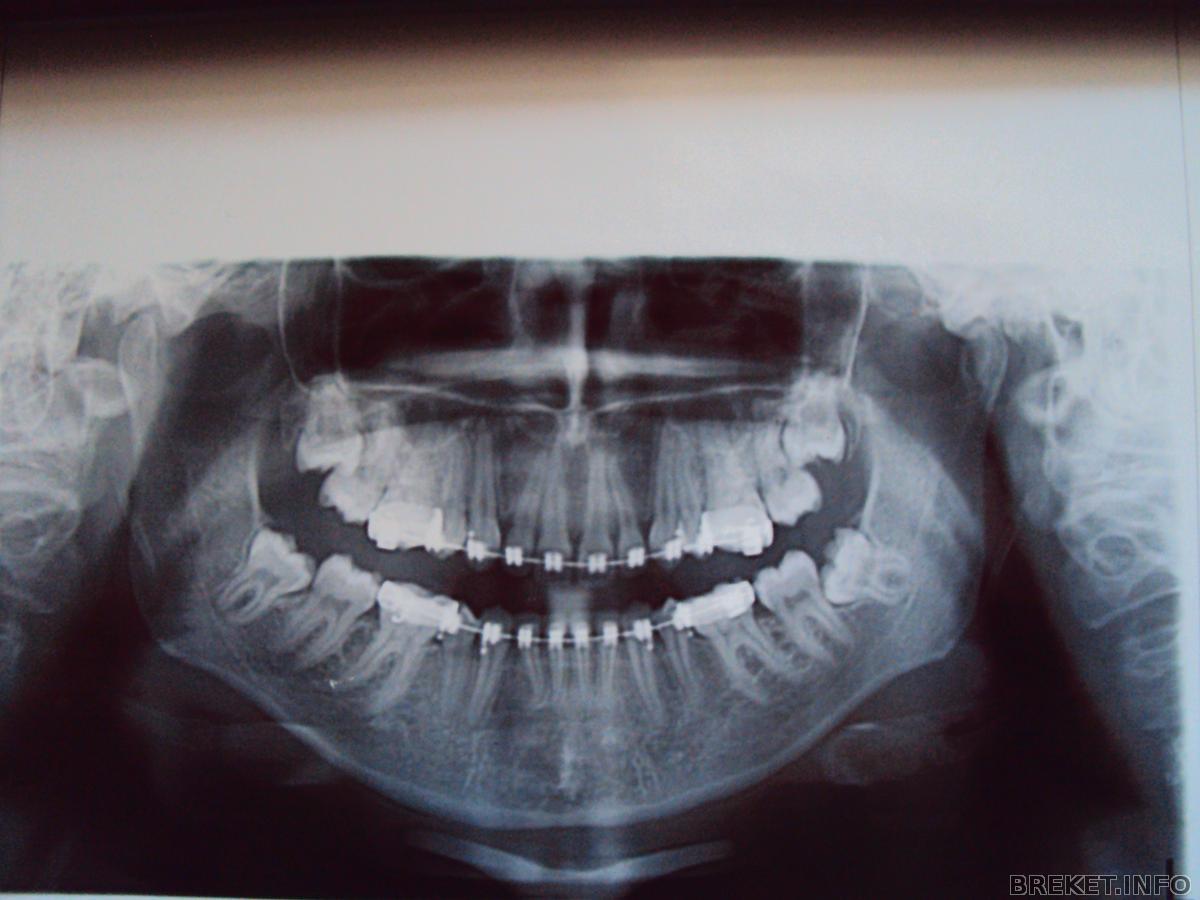

Пришла я значит с повторным снимком к своей ортофеечке, а она смотрит, решает где чего подтянуть и говорит страшнейшее из моих ожиданий: Ну что, 8-ки то будем удалять? я говорю: а что надо? я думала она имела ввиду удаление тех восьмерок которые в десне лежат а оказывается она про те которые сверху ровно стоят и удалять их не потому что мешают а потому что я их плоховато прочищаю. Я сказала что теперь буду стараться и она вроде как согласилась, потому что она сказала чистить лучше. Ух. Потом мне одели железную лигатуру на ВЧ (проволочку тоненькую) еще плюс и чейн поменяли и на НЧ и на ВЧ. Читать далее »

dsc00573.jpg

Ребята,как считаете стоит ли удалять восьмерки из десны?какова вероятность,что когда они решат вылезти,остальные зубы сдвинуться?